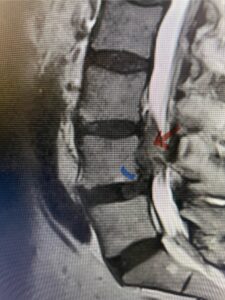

The next patient is a 56-year-old morbidly obese female who had progressive leg pain and weakness. She was over 320 lbs and did not have diabetes either. On MRI she had a massive disc herniation spanning the L3-4 and L-4 interspaces, centered behind the L4 vertebral body (Fig 3A and B). She also had an L4-5 spondylolisthesis. There were opinions that the disc emanated from the L3-4 disc space, but because of spondylolisthesis and on careful inspection of the MRI, there was a high chance the disc herniation had instead emanated from L4-5 (Fig 4). She had conservative treatment including epidurals but had worsening strength and numbness. She was scheduled electively for surgery, but then fell, and broke her ankle. She could not walk, particularly due to the pain down her leg. She was taken to the operating room urgently after she was cleared medically. She had no issues cardiologically and was taken to the operating room. The patient underwent a laminectomy that extended above the L3-4 disc space to below the L4-5 disc space. We encountered mainly centered on the left at the level of the L4 vertebral body and massive disc herniation that created a huge cavity in the lumbar canal. It was covered in an interesting thin membrane that we dissected off the disc herniation (Fig 5). Postoperatively the patient did experience significant relief of pain, but some improvement of strength. In combination with the ankle fracture and the extent of preoperative weakness, the patient required extensive rehab. The patient also developed a seroma and some wound drainage issues that were treated locally.

Fig. 3a : Sagittal T2-weighted lumbar MRI demonstrating a massive L4-5 disc herniation with superior migration behind the L4 vertebral body and taking up most of the left side of the spinal canal (red arrow) Note the slight grade one spondylothesis at L4-5 (blue dash). Notice the severe compression of the thecal sac (blue arrow) by the large left sided disc herniation (red arrow)

Fig 4: Sagittal T2-weighted lumbar MRI demonstrating an L4-5 grade 1 spondylolisthesis with obvious emanation of the disc herniation from the L4-5 level (red arrow)